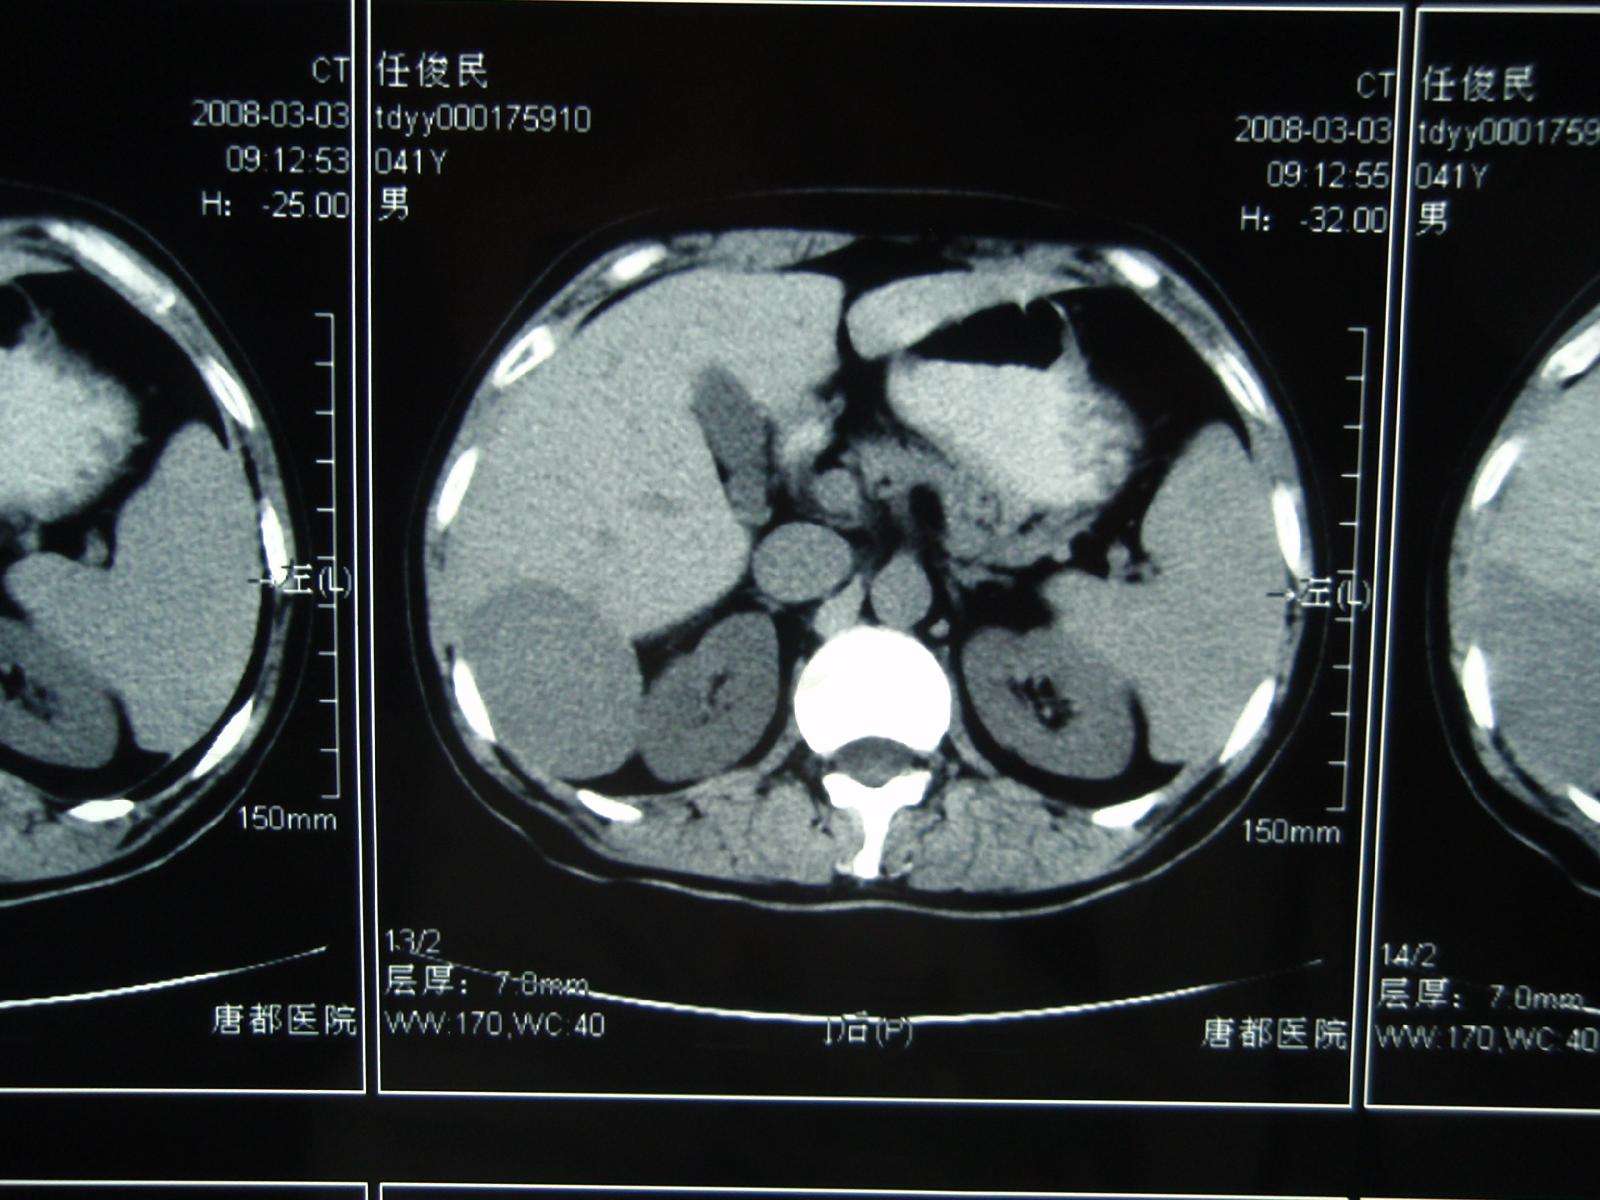

李某,女,35岁,肝区不适,2008年3月3日CT发现肝右后叶占位性病变,增强扫描确诊巨大肝血管瘤。

2008年3月5日张洪新教授做介入DSA造影明确诊断: